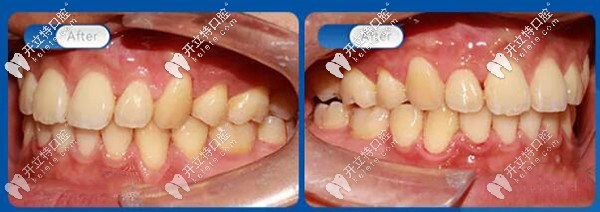

45度看,解除牙列擁擠,解除牙弓前凸,解除磨牙深覆蓋,恢復(fù)正常咬合關(guān)系。

解除牙弓前凸

從口內(nèi)45°左右側(cè)面照對比可以看到上牙列不齊,牙弓前凸,磨牙深覆蓋,上下牙列重度擁擠,上下咬合關(guān)系不協(xié)調(diào)。

上下咬合關(guān)系不協(xié)調(diào)